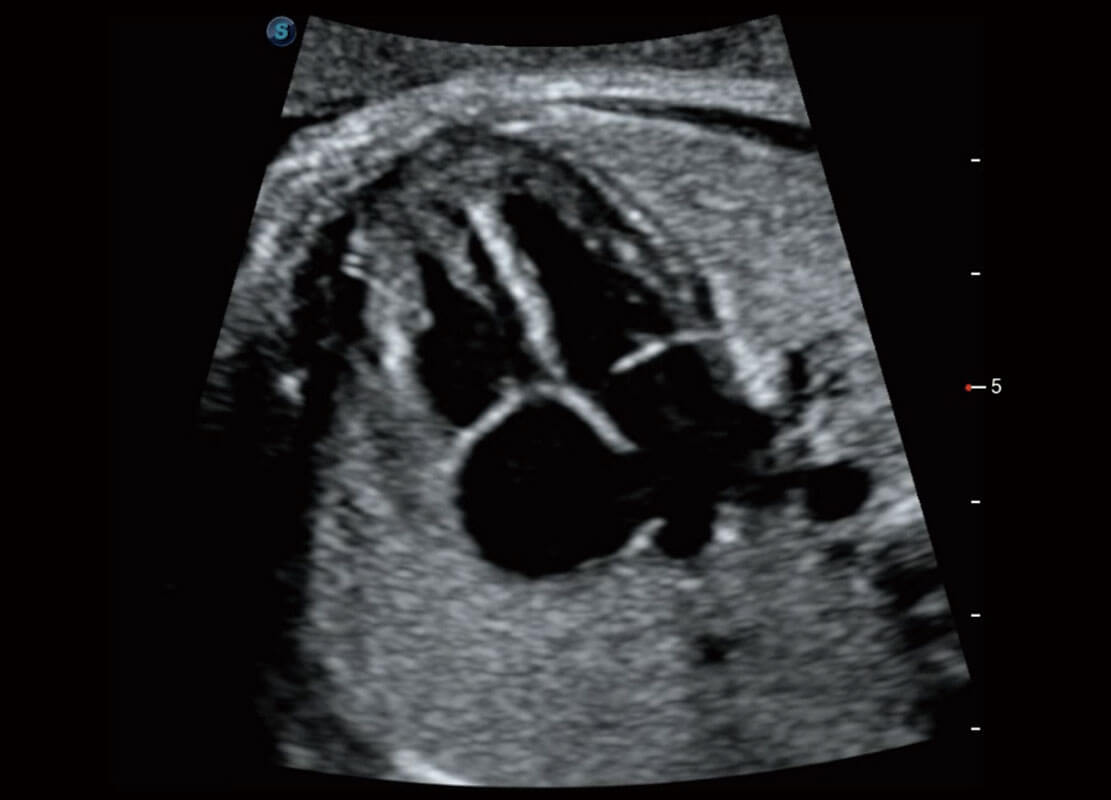

四腔切面